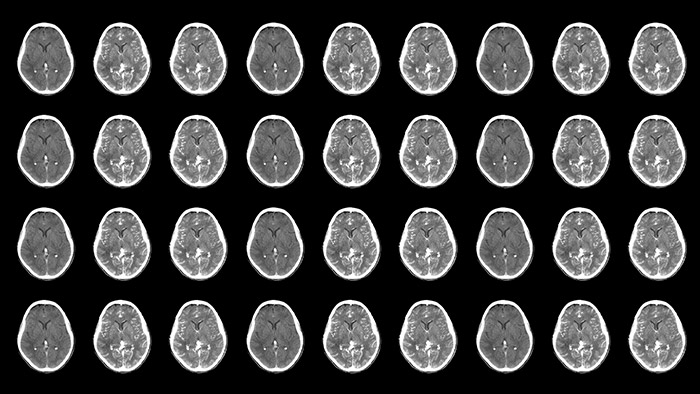

Improved neuro CT-like cone beam CT images (CBCT) to identify ischemic changes in the Angio suite. The advanced protocol with dual-axis acquisition trajectory and improved reconstruction software results in improved image appearance, compared to conventional CBCT acquisition techniques.